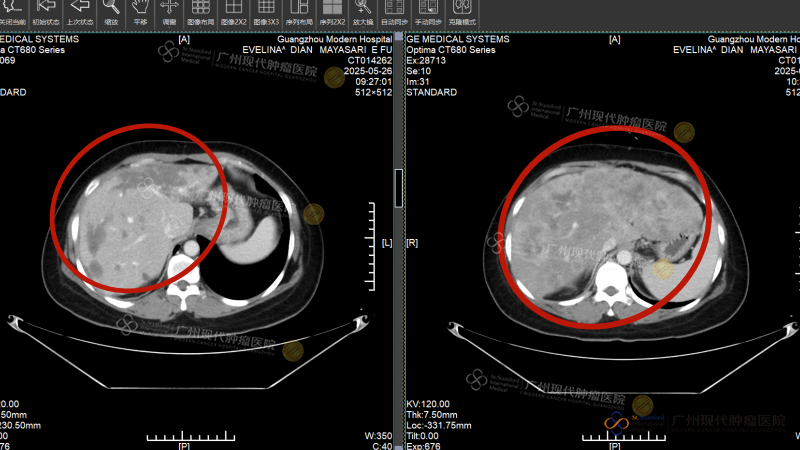

Empat minggu kemudian, Intervensi kedua benar-benar membawa keajaiban: Tumor metastasis di hati menyusut dari 16cm menjadi sekitar 2 cm, asites menghilang, dan fungsi hati perlahan kembali normal. Pemeriksaan pencitraan ulang menunjukkan: benjolan di payudara dan lesi di hati menyusut drastis, sebagian bahkan mengalami nekrosis. Saat Evelina mengambil foto liburan di pinggir jalan Guangzhou dan mengirimkannya kepada teman-teman di kampung halamannya, balasan yang ia terima semuanya sama:“Kamu yakin diagnosisnya tidak salah? Ini tidak terlihat seperti pasien kanker!”

Sebelum pengobatan, tumor hati berukuran sekitar 16cm; setelah pengobatan, tumornya telah kehilangan aktivitas